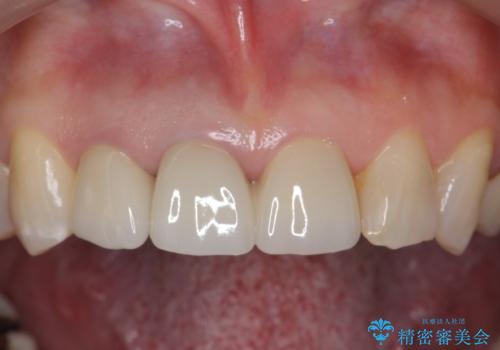

右上の前歯二本、左上の前歯1本をセラミックにし、正中の前歯を2本連結しました。

連結しなくても、ナイトガード使用で防止できると説明しましたが、手間をかけずに二度と広がらない方がいいとのことで連結を強くご希望でした。

- 60.5万円(税込み) ジルコニアクラウンスペシャル 14.3万円x3 仮歯 1.1万円x3 右上1、右上2:ファイバーコア 2.2万円x2 右上1: 精密根管治療(リトリートメント) 9.9 万円x1費用は治療当時の料金となります

気になっていたすき間が閉じて、大変喜んでいただけました。

歯周病や楽器の影響などですき間が生じることはありますが、今回は開いてきた原因はわからないため、連結するか、ナイトガードをはめて歯ぎしりで力がかかりすぎないようにすることが大事になってきます。